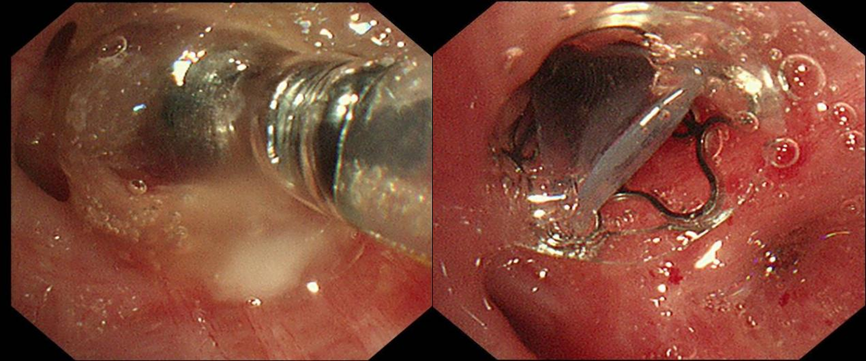

基于首次检查结果,医疗团队针对目标靶区精准实施支气管镜治疗。通过冷冻技术处理瘘口局部组织,促进组织修复反应,同时填塞可吸收明胶海绵。明胶海绵迅速填充瘘口,物理阻断气体泄漏,手术过程中患者未见明显漏气。然而,一周后患者再次出现漏气症状,提示单纯冷冻与明胶海绵填塞未能彻底解决问题,治疗需进一步升级。

面对再次漏气,医疗团队果断进行再一次支气管镜介入。先置入可吸收明胶海绵,进行初步封堵,为后续操作创造更好条件。随后,精准释放EBV活瓣(EBV-TS-4.0),活瓣如同“智能阀门”,吸气时开放保证通气,呼气时关闭阻断气体漏入胸膜腔。术后膨肺并负压吸引,观察一分钟,引流瓶未见气泡溢出。三次支气管镜介入,阶梯式推进治疗,最终实现对支气管胸膜瘘的“精准打击”。